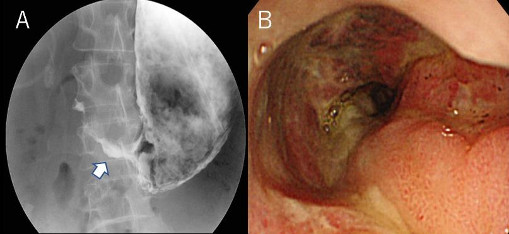

図2. 胃十二指腸閉塞における消化管造影検査、内視鏡検査3. 治療

図4. 胃十二指腸閉塞に対する

ステント留置のレントゲン写真

食道、胃、十二指腸の場合には口から内視鏡を、大腸の場合にはおしりから内視鏡を挿入し、消化管閉塞を認めている部位まで内視鏡を誘導します。閉塞部分で再度造影検査を行い、実際の閉塞部位の長さや屈曲状況などを確認します。ガイドワイヤーを閉塞部分より奥まで誘導して、閉塞部分を十分覆う形でガイドワイヤーに沿わせて消化管ステントを留置して、閉塞を解除します。

消化管ステントは針金でできており、留置すると自己拡張力によって徐々に拡張していき、閉塞部分を押し広げていきます。留置後2-3日で多くの場合、完全拡張してきます。それにより癌によって閉塞した消化管を内腔から押し広げ、針金で裏打ちする形となります。